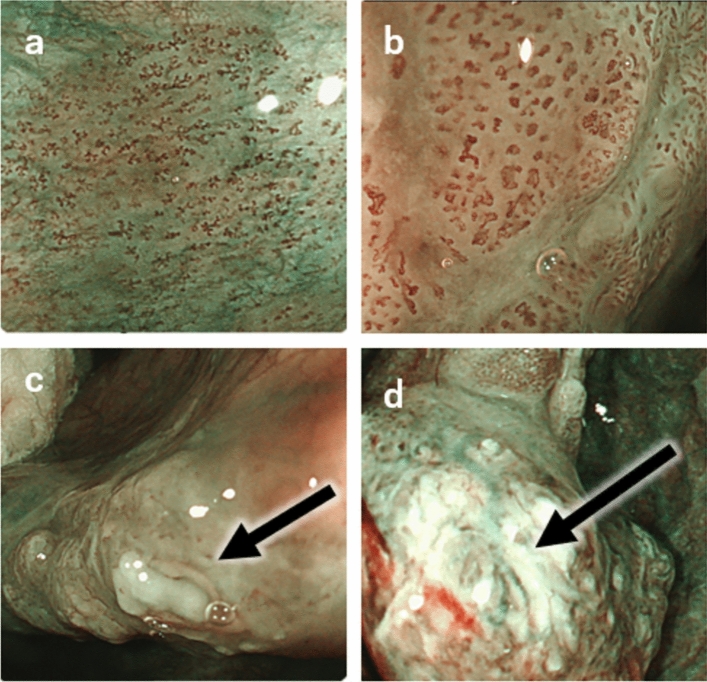

浅表性喉咽癌(SLPC)被定义为“癌细胞局限于上皮下层,未侵犯固有肌层,伴或不伴淋巴结转移”的癌症阶段。随着内镜技术和观察方法的进步,近年来报道了大量的SLPC病例。微创口腔切除方法,使器官保存,也已开发用于治疗SLPC。但需要注意的是,SLPC的诊断是基于肿瘤的厚度,不能通过TNM分类来解决。此外,尽管SLPC通常预后良好,但一定比例的患者发生淋巴结转移和/或多发异时性肿瘤,这两种情况都可能对预后产生不利影响。此外,对于最佳的治疗后监测和影响淋巴结转移风险的因素尚未积累足够的证据,需要进一步研究。本文综述了SLPC的流行病学、一般特征、诊断、治疗和预后。

Superficial laryngo-pharyngeal cancer (SLPC) is defined as that stage of the cancer in which "cancer cells are confined to the subepithelial layer, without invasion of the muscularis propria, with or without lymph node metastasis." With the advances in endoscopic technologies and observation methods, numerous cases of SLPC have been reported in recent years. Less invasive oral resection methods, enabling organ preservation, have also been developed for the treatment of SLPC. However, it should be noted that the diagnosis of SLPC is based on the tumor thickness, which cannot be addressed by the TNM classification. Furthermore, although SLPC is generally associated with a good prognosis, a certain proportion of patients develop lymph node metastasis and/or multiple metachronous cancers, both of which may be expected to have an adverse impact on the prognosis. In addition, sufficient evidence has not accumulated for optimal post-treatment surveillance and factors affecting the risk of lymph node metastasis, and further investigation is required. In this review, we describe the epidemiology, general characteristics, diagnosis, treatment, and prognosis of SLPC.